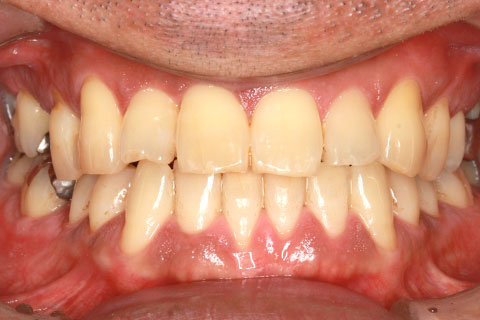

フルリンガル矯正2:上下の歯を舌側矯正で治療(矯正期間18ヶ月)

- 年齢・性別

- 42歳男性

- 治療期間

- 1年6ヶ月

- 抜歯

- なし

- 治療費

- 120万円(税込み)

- 備考

- マルチブラケットを用いた矯正治療

- 治療内容

- 反対咬合をフルリンガル矯正治療にて改善

- 施術の副作用(リスク)

- 表側矯正と比較して、歯根の角度を確立する「トルク」の力がかかりにくい。